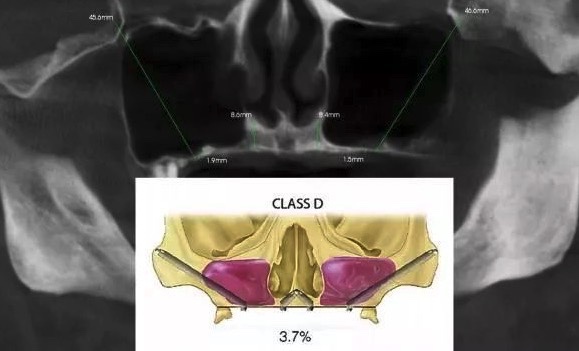

术前必读

因为颧种植体的长度是传统植体的 3~4 倍,因此起点的微小误差就可导致末端的偏离,所以术前应详细进行手术计划,CT 检查对于了解双侧颧骨的情况必不可少。患者还应进行常规的全身及口腔颌面部的专科检查,排除相关禁忌症的存在。